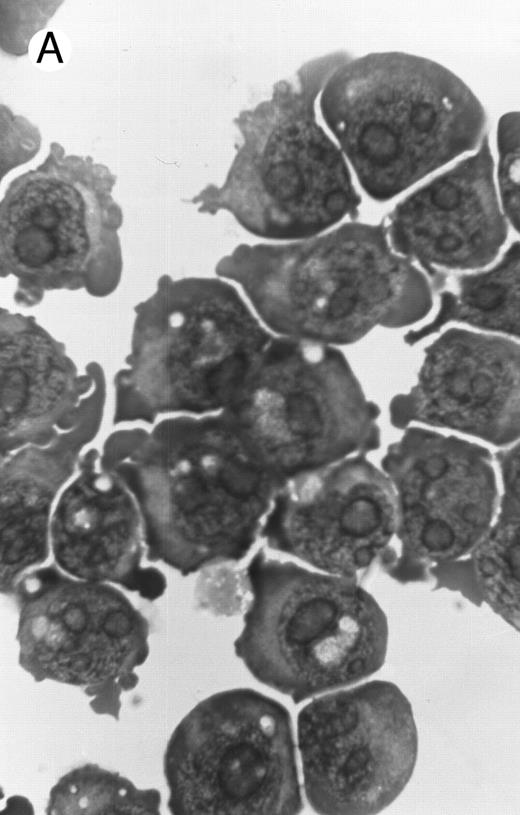

Morphology of PLB-985 cells (A) before treatment and after a 4-day treatment with (B) 1.25% DMSO (differentiation) or (C) 10−7 mol/L 9-cis-RA (apoptosis) (original magnification × 1,000).

We have shown above that activation of both RAR and RXR by 9-cis-RA or by the combination of selective ligands inhibits cell growth and induces cell death in PLB-985 cells. We wished to verify whether these retinoids also induced differentiation of PLB-985 cells before the onset of cell death. Microscopic examination of cell morphology after 4 days of treatment with 9-cis-RA demonstrated no differentiated phenotype (Fig 2C). On the other hand, DMSO-treated PLB-985 cells had a typical differentiated morphology (Fig 2B). We then examined alterations in several cell surface markers, especially those specific for differentiated granulocytes. We contrasted the known differentiation effects of retinoids on NB4 with PLB-985 cells. NB4 and PLB-985 cells express low levels of CD11b and no detectable CD11c, but high levels of CD13.2 44 As previously reported, treatment of NB4 cells with 9-cis-RA increases expression of CD11b and CD11c, and significantly reduces expression of CD13 (Fig 3, bottom), consistent with the differentiation of NB4 cells into granulocytes. Also consistent with their effects on cell growth, the RXR-selective ligand 100153 did not have any effect on the surface marker expression in NB4 cells, but the RAR-selective ligand 100272 induced the same differentiation-specific changes as 9-cis-RA. In PLB-985 cells, DMSO-induced granulocytic differentiation stimulates the surface expression of CD11b44 (and data not shown). In our experiments PLB-985 cells treated with 9-cis-RA did not show any increase in CD11b and CD11c levels. These cells also continued to express high levels of CD13, even at day 4, when the cell counts began to decrease (Fig 3, top). As expected, the selective ligands, either alone or in combination, also did not have any effect on the expression of these markers in PLB-985 cells. These results show that stimulation of both RAR and RXR inhibits growth and induces cell death without differentiation in PLB-985 cells.

Induction of apoptosis by 9-cis-RA. Microscopic observation of retinoid-treated PLB-985 cells showed typical characteristics of apoptosis, including cell shrinkage, membrane blebbing, and nuclear fragmentation (Fig 2C). Furthermore, apoptotic cells were observed as early as 2 days after the addition of retinoids, and increased in numbers with the progression of treatment (data not shown). A typical molecular characteristic of apoptosis is genomic DNA cleavage into internucleosomal segments attributed to the specific activation of an endogenous endonuclease.45 Several cell lines (MOLT-3, T-cell ALL; CEM, T-cell ALL; PLB-985; Raji, Burkitt lymphoma; HUT 78, cutaneous T-cell lymphoma) were treated for 4 days with 10−6 mol/L 9-cis-RA. DNA was isolated from these cultures, separated on an agarose gel, and visualized by ethidium bromide staining. Only RA-treated PLB-985 cells exhibited a typical apoptotic “DNA laddering” pattern (data not shown). Similar results were obtained after treatment with all-trans-RA and 13-cis-RA (data not shown); however, this effect was most pronounced with 9-cis-RA.